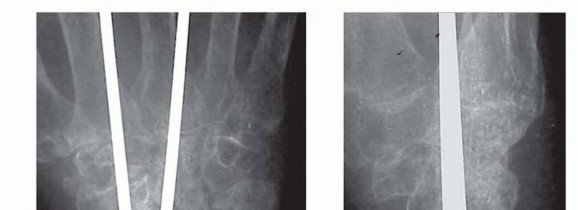

TECH FIG 2 • A,B. Complex wrist collapse secondary to rheumatoid arthritis treated with an intramedullary rod and wiring. Ulnar impaction symptoms developing at the distal radioulnar joint. C,D. Less severe wrist disease in a different patient was treated with a Darrach resection and wrist arthrodesis.(continued)

TECH FIG 2 •(continued)E,F. PA and lateral radiographs after wrist arthrodesis in a different patient with rheumatoid arthritis was undertaken using two Steinmann pins inserted through the second and third and third and fourth intermetacarpal spaces. (A-D: Courtesy of P.J. Stern, MD; E,F: Copyright Thomas R. Hunt III, MD.)